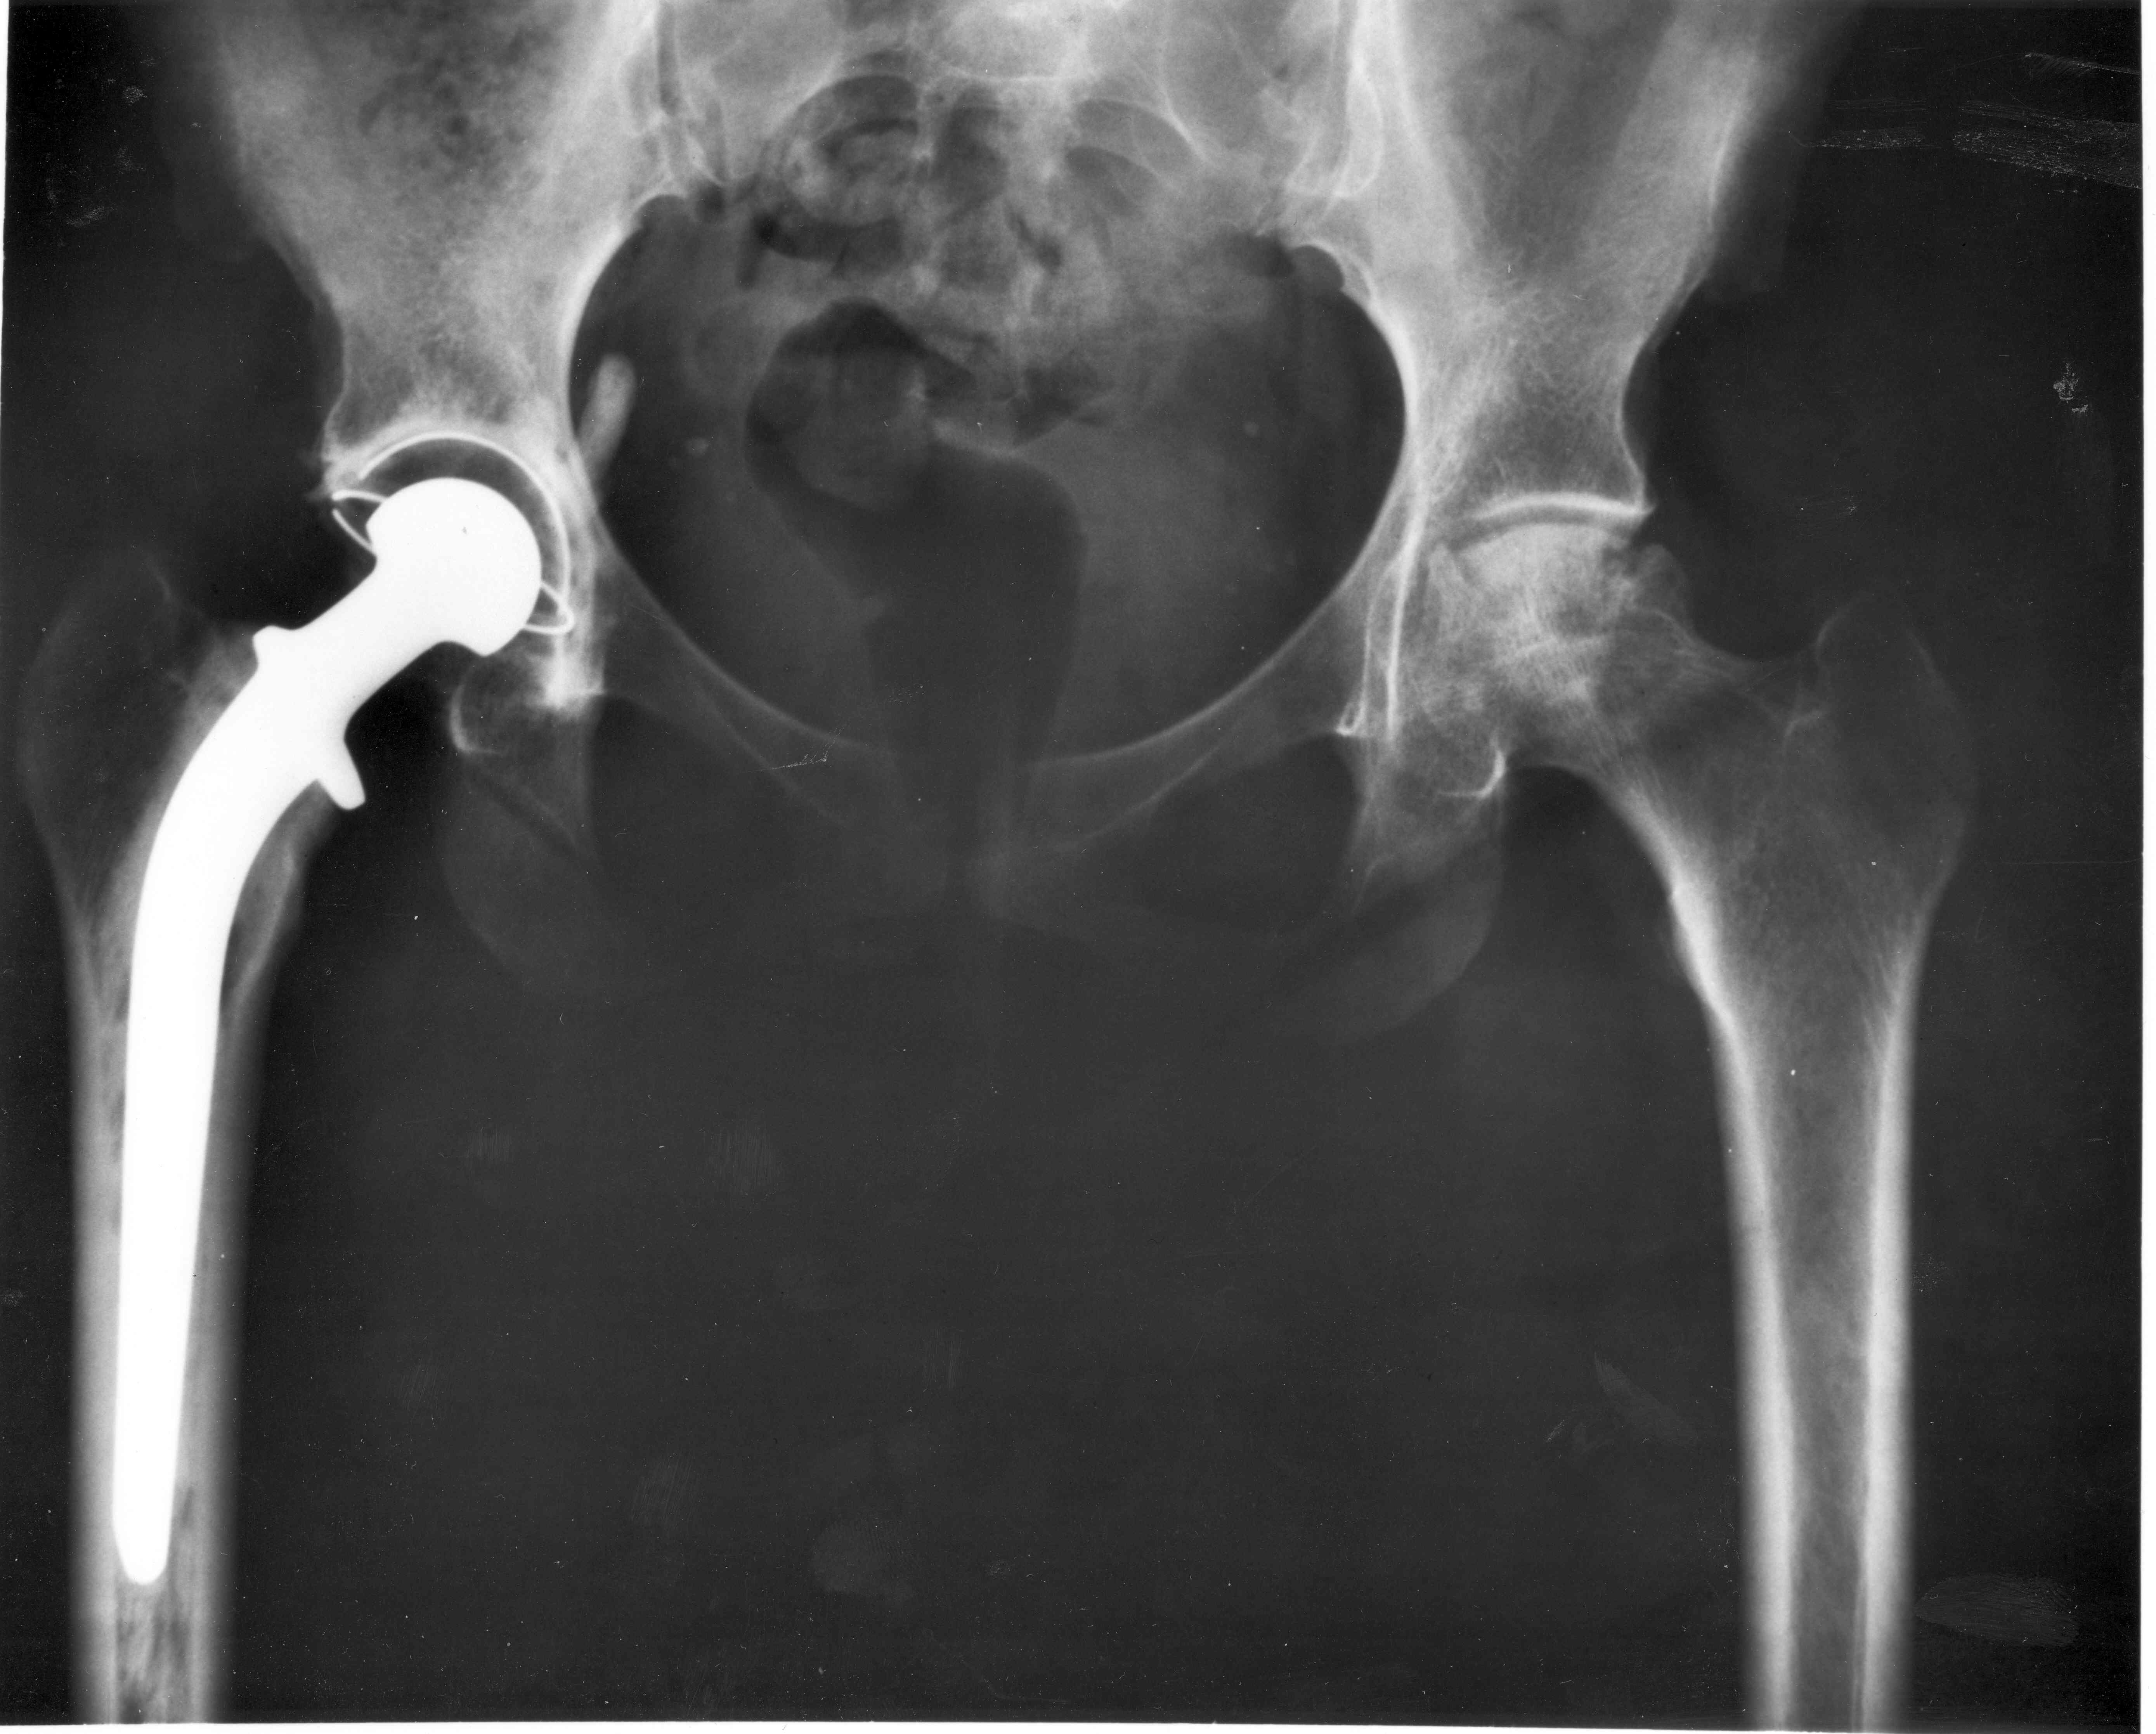

By X-ray Image ID: 3684. Photographer: Unknown. - from NIH Here. Credit: NIADDK, 9AO4 (Connie Raab-contact); NIH., Public Domain, https://commons.wikimedia.org/w/index.php?curid=789996

A study of over 1.9 million total hip replacements using modern materials suggests that most will last at least three decades. Australian and international researchers used data from national registries and previous clinical studies spanning 18 countries, looking at the materials from which the hips were made and the time from initial replacement to when the first follow up surgery was needed. Based on up to 20 years of real data and projections up to 30 years, they found over 92% of the hips made from three different types of modern materials would last 30 years, compared to previous research finding less than 58% of replacement hips would last 25 years. This is likely due to less wear on the modern materials from which modern hip implants are made, the study authors say.

Modern hip replacements [1] are nearly twice as likely as older hip replacements [2] to last at least 25 years, suggests a new study published in The Lancet. The authors of the systematic review and meta-analysis employed advanced modeling techniques to estimate that 92% of modern hip replacements are likely to last at least 25 years. This represents a significant improvement compared to earlier studies on older hip replacement technologies, which indicated that approximately 58% of such implants could reach the 25-year mark.

Hip replacements are highly successful operations that help millions of people worldwide regain mobility and improve their quality of life. As more young patients undergo the procedure and people live longer, it is increasingly important to know how long these implants last. Over the past two decades, advances in the materials used for hip replacements have greatly reduced wear and may have improved their longevity. However, until now, there hasn’t been a large-scale study looking at how long these modern hip replacements truly last. The most recent major estimate, from a 2019 Lancet study [3], suggested that only about 58% of implants were still working after 25 years, but that analysis included older materials no longer in use, which were more likely to wear out or break.

The current study included data from eight national joint registries, covering nearly 1.9 million hip replacements, and clinical studies involving over 5,000 patients. The analysis found that around 93% of modern hip replacements last at least 20 years, and further modelling suggests that 91% could keep working well for at least 30 years. The authors highlight that while the results are reassuring at the population level, they don’t necessarily predict how long a hip replacement will last for each individual, with factors such as a person’s age, overall health, bone quality, and the surgical technique used all affecting outcomes.

[1] Modern hip replacements use more durable materials such as highly cross-linked polyethylene (XLPE) and newer types of ceramics, which became the standard treatment worldwide by 2008

[2] Older hip replacements used ultra-high-molecular-weight polyethylene (UHMWPE) for the hip socket or liner, which can wear and trigger inflammation, leading to bone loss and the implant loosening